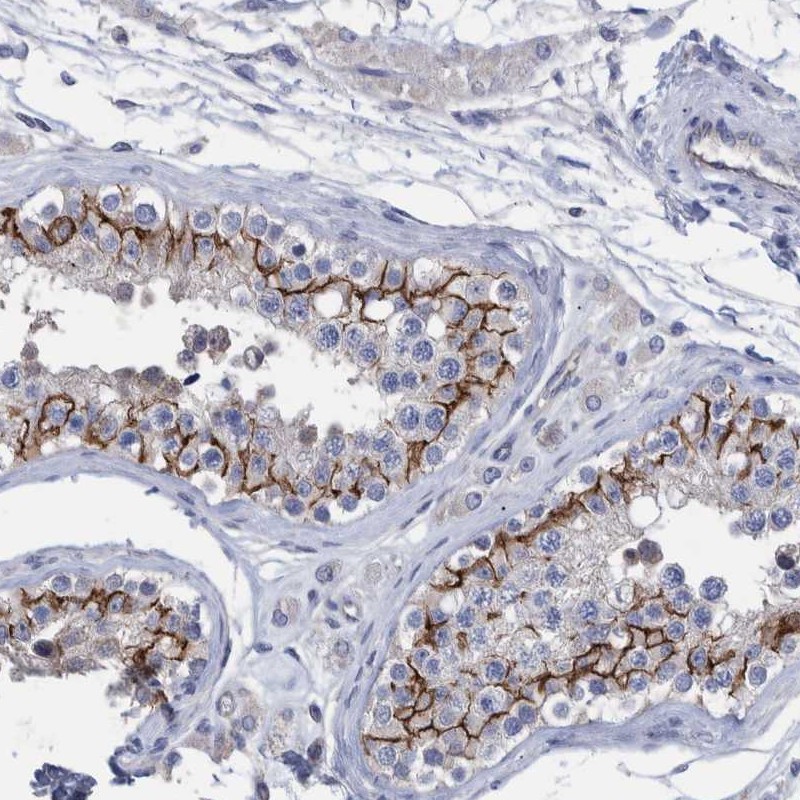

Immunohistochemical staining of human testis shows distinct membranous positivity in cells in seminiferus ducts.